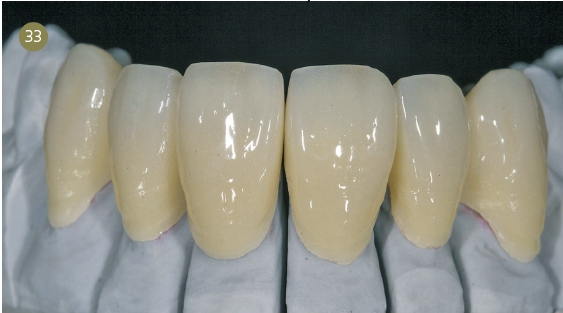

Wax-up

Es half der Patientin sehr, das Wax-up auf dem Gipsmodell anzuschauen. Gute Erfahrungen, in bestimmten Fällen ein Waxup zu fertigen und es mit dem Behandler zusammen mit den Patienten zu besprechen, machen wir immer wieder. Gerade bei Patienten mit einer hohen Erwartung ist es essenziell, sie in die Behandlungsplanung mit einzubeziehen und laienverständlich vorzugehen. So haben wir auch der Patientin genau dargelegt, wie wir zu ihrer neuen Zahnform kamen. Mithilfe des „Digital Smile Design“ nach Dr. Christian Coachman zeigten wir ihr unsere Vorstellung der bestmöglichen Versorgung. Dies ist für mich unerlässlich in der täglichen Arbeit geworden. Auch die Patienten lieben diese Art der Kommunikation zusätzlich zum Wax-up auf dem Gipsmodell.